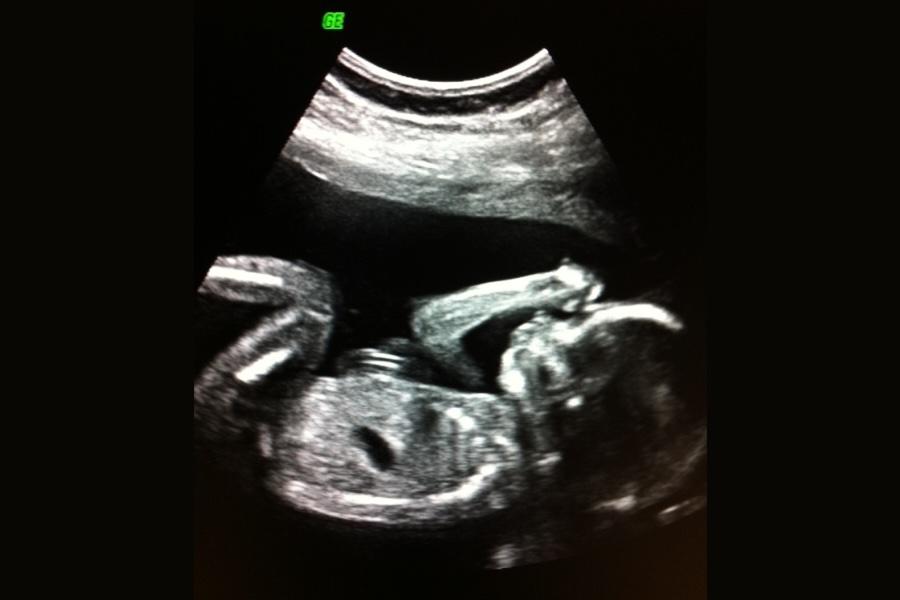

Tillväxtkontroll för att se hur barnet växer Till utökad fosterdiagnostik räknas också tillväxtkontroll med ultraljud, ofta kallad TVK. Vid undersökningen uppskattas barnets vikt och jämförs med den förväntade vikten för graviditetslängden. En TVK görs rutinmässigt om du till exempel tidigare fött ett tillväxthämmat barn, har en diagnos eller riskfaktor som kan påverka barnets tillväxt, eller om ditt SF-mått är avvikande.

Om undersökningen görs vid ett tillfälle kallas det viktskattning. Görs den flera gånger kan man följa barnets tillväxt över tid. I vissa fall kontrolleras även blodflödet i navelsträngen och mängden fostervatten för att få en helhetsbild av hur barnet mår.